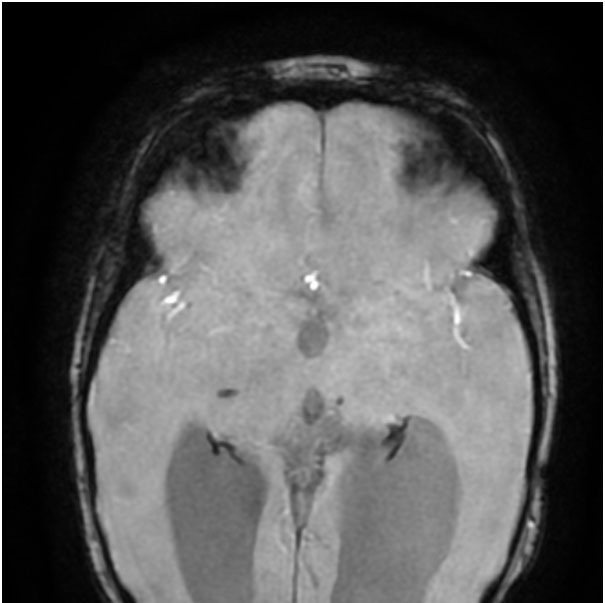

Hence, the first step in the diagnostic process is getting an MRI of the brain done. Neuroimaging in this patient (Figure 1 A-B) suggested a structural etiology (Porencephalic cysts).

Presence of porencephalic cysts with microhemorrhages in deep gray matter and periventricular and subcortical white matter, are the hallmark radiological features. Other imaging findings include diffuse periventricular leukoencephalopathy, lacunar infarcts, and dilated perivascular spaces.

Figure 1A:

T2W axial MRI brain – Bilateral periventricular white matter paucity (L>R) with porencephalic cysts and ex-vacuo dilation of bilateral lateral ventricles